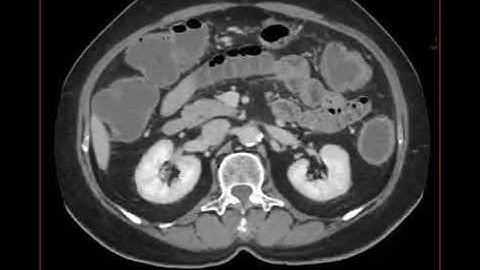

Chẩn đoán hinh ảnh: cấp cứu bụng và Tắc ruột